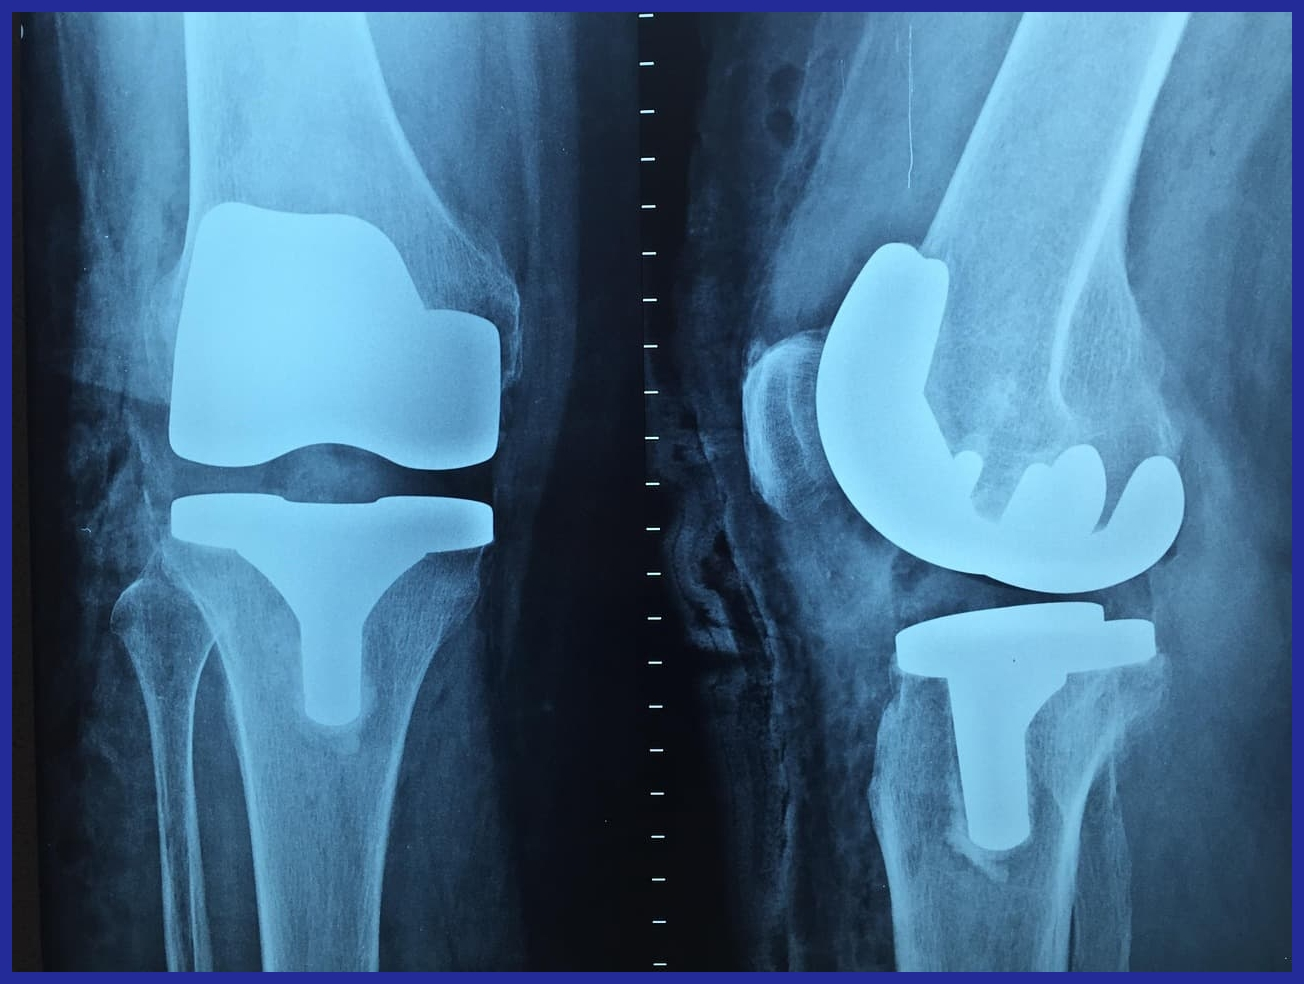

무릎 관절 건강, 제대로 관리해야 평생 편안하다! 관절 유지 방법 총정리

무릎 관절은 걷기, 뛰기, 앉기 등 일상생활에서 가장 많이 사용하는 관절 중 하나입니다.하지만 노화, 잘못된 생활 습관, 체중 증가 등으로 인해 연골 손상 & 퇴행성 관절염 위험이 높아질 수 있

무릎 관절 통증 vs 무릎 관절염 초기 증상: 차이점과 올바른 대처법

무릎은 우리 몸에서 가장 많이 사용되는 관절 중 하나로, 체중을 지탱하고 걷기, 뛰기, 앉기 등의 다양한 움직임을 담당합니다. 하지만 무릎을 반복적으로 사용하면 통증이 발생할 수 있으며,